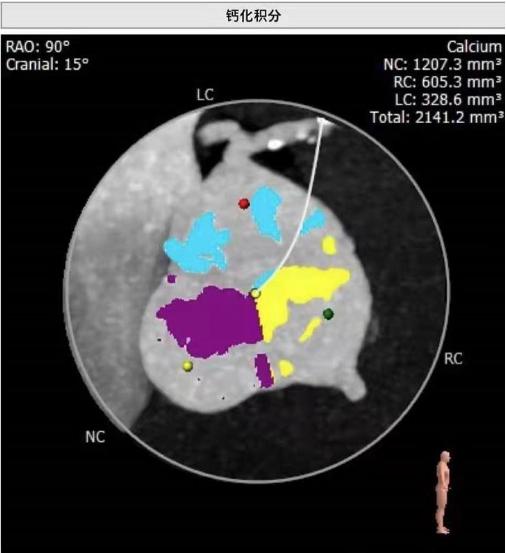

心内科主任医师何晋发现杨爷爷心脏杂音很重,怀疑心脏瓣膜出了问题,经心脏超声检查,果不其然,杨爷爷的心脏有个大“BUG”——主动脉瓣重度狭窄伴中度关闭不全,也就是心脏的阀门坏了,导致他主动脉瓣上下的压差高达70mmHg,而严重的瓣膜病变引发了心脏肥厚、心功能受损,检查还发现他的冠状动脉病变也很严重。

杨爷爷年龄大、心功能差,不能接受外科手术,但如果保守治疗,这类患者的两年生存率不到50%。综合考虑下,何晋主任医师团队多次讨论,最终为杨爷爷制定了经导管主动脉瓣置换及冠脉支架(TAVI+PCI)手术方案,不需要开胸,降低了手术风险。经过精心术前准备,何晋主任医师团队联合心外科、体外循环、麻醉科、介入手术部等多学科,为杨爷爷完成了高难度、超高龄的经导管主动脉瓣置换联合冠脉介入术。